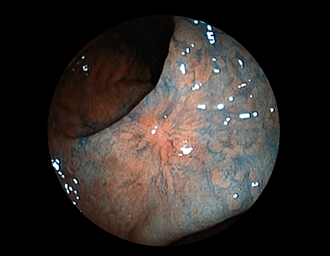

症例1:胃潰瘍(37才、男性)

①胃潰瘍(Stage A1)

健診:胃レントゲン検査で、胃角部ニッシェを指摘され当院受診。

胃角部小弯に、深くて大きな、大きさ約10mmの胃潰瘍(stage 1)

があり、潰瘍底は一部白苔はみ出しを認める。エソメプラゾールマグネシウム水和物投薬で治療開始しました。

(FICE画像)